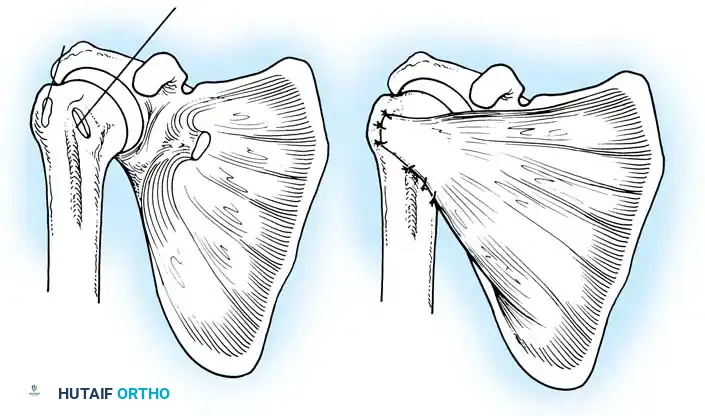

Glenoid Preparation and Labral Repair

The essential step in restoring stability is the anatomical reduction of the capsulolabral complex to a bleeding bone bed on the anterior glenoid rim.

- Debridement: The anterior glenoid neck is decorticated using a motorized burr, rasp, or osteotome to create a bleeding cancellous bed. This promotes robust biological healing of the repaired labrum.

- Mobilization: The scarred, medially displaced labrum (ALPSA lesion) must be fully mobilized using a periosteal elevator until the subscapularis muscle belly is visible anteriorly. The tissue must float freely to be shifted superiorly and laterally.

- Anchor Placement: Suture anchors (typically 3 to 4) are placed along the articular margin of the anteroinferior glenoid (from the 5:30 to 3:00 positions for a right shoulder). Anchors must be inserted at a 45-degree angle to the articular surface to maximize pullout strength and avoid joint penetration.

Capsular Shift and Closure

To address capsular redundancy, an inferior capsular shift is performed.

- The arm is positioned in 30 to 45 degrees of abduction and 20 degrees of external rotation.

- The inferior capsular flap is advanced superiorly and laterally, tensioning the IGHL complex. The sutures from the anchors are passed through the shifted capsule and tied.

- The superior flap is then brought down over the inferior flap in a "pants-over-vest" fashion to reinforce the anterior wall and close the rotator interval.